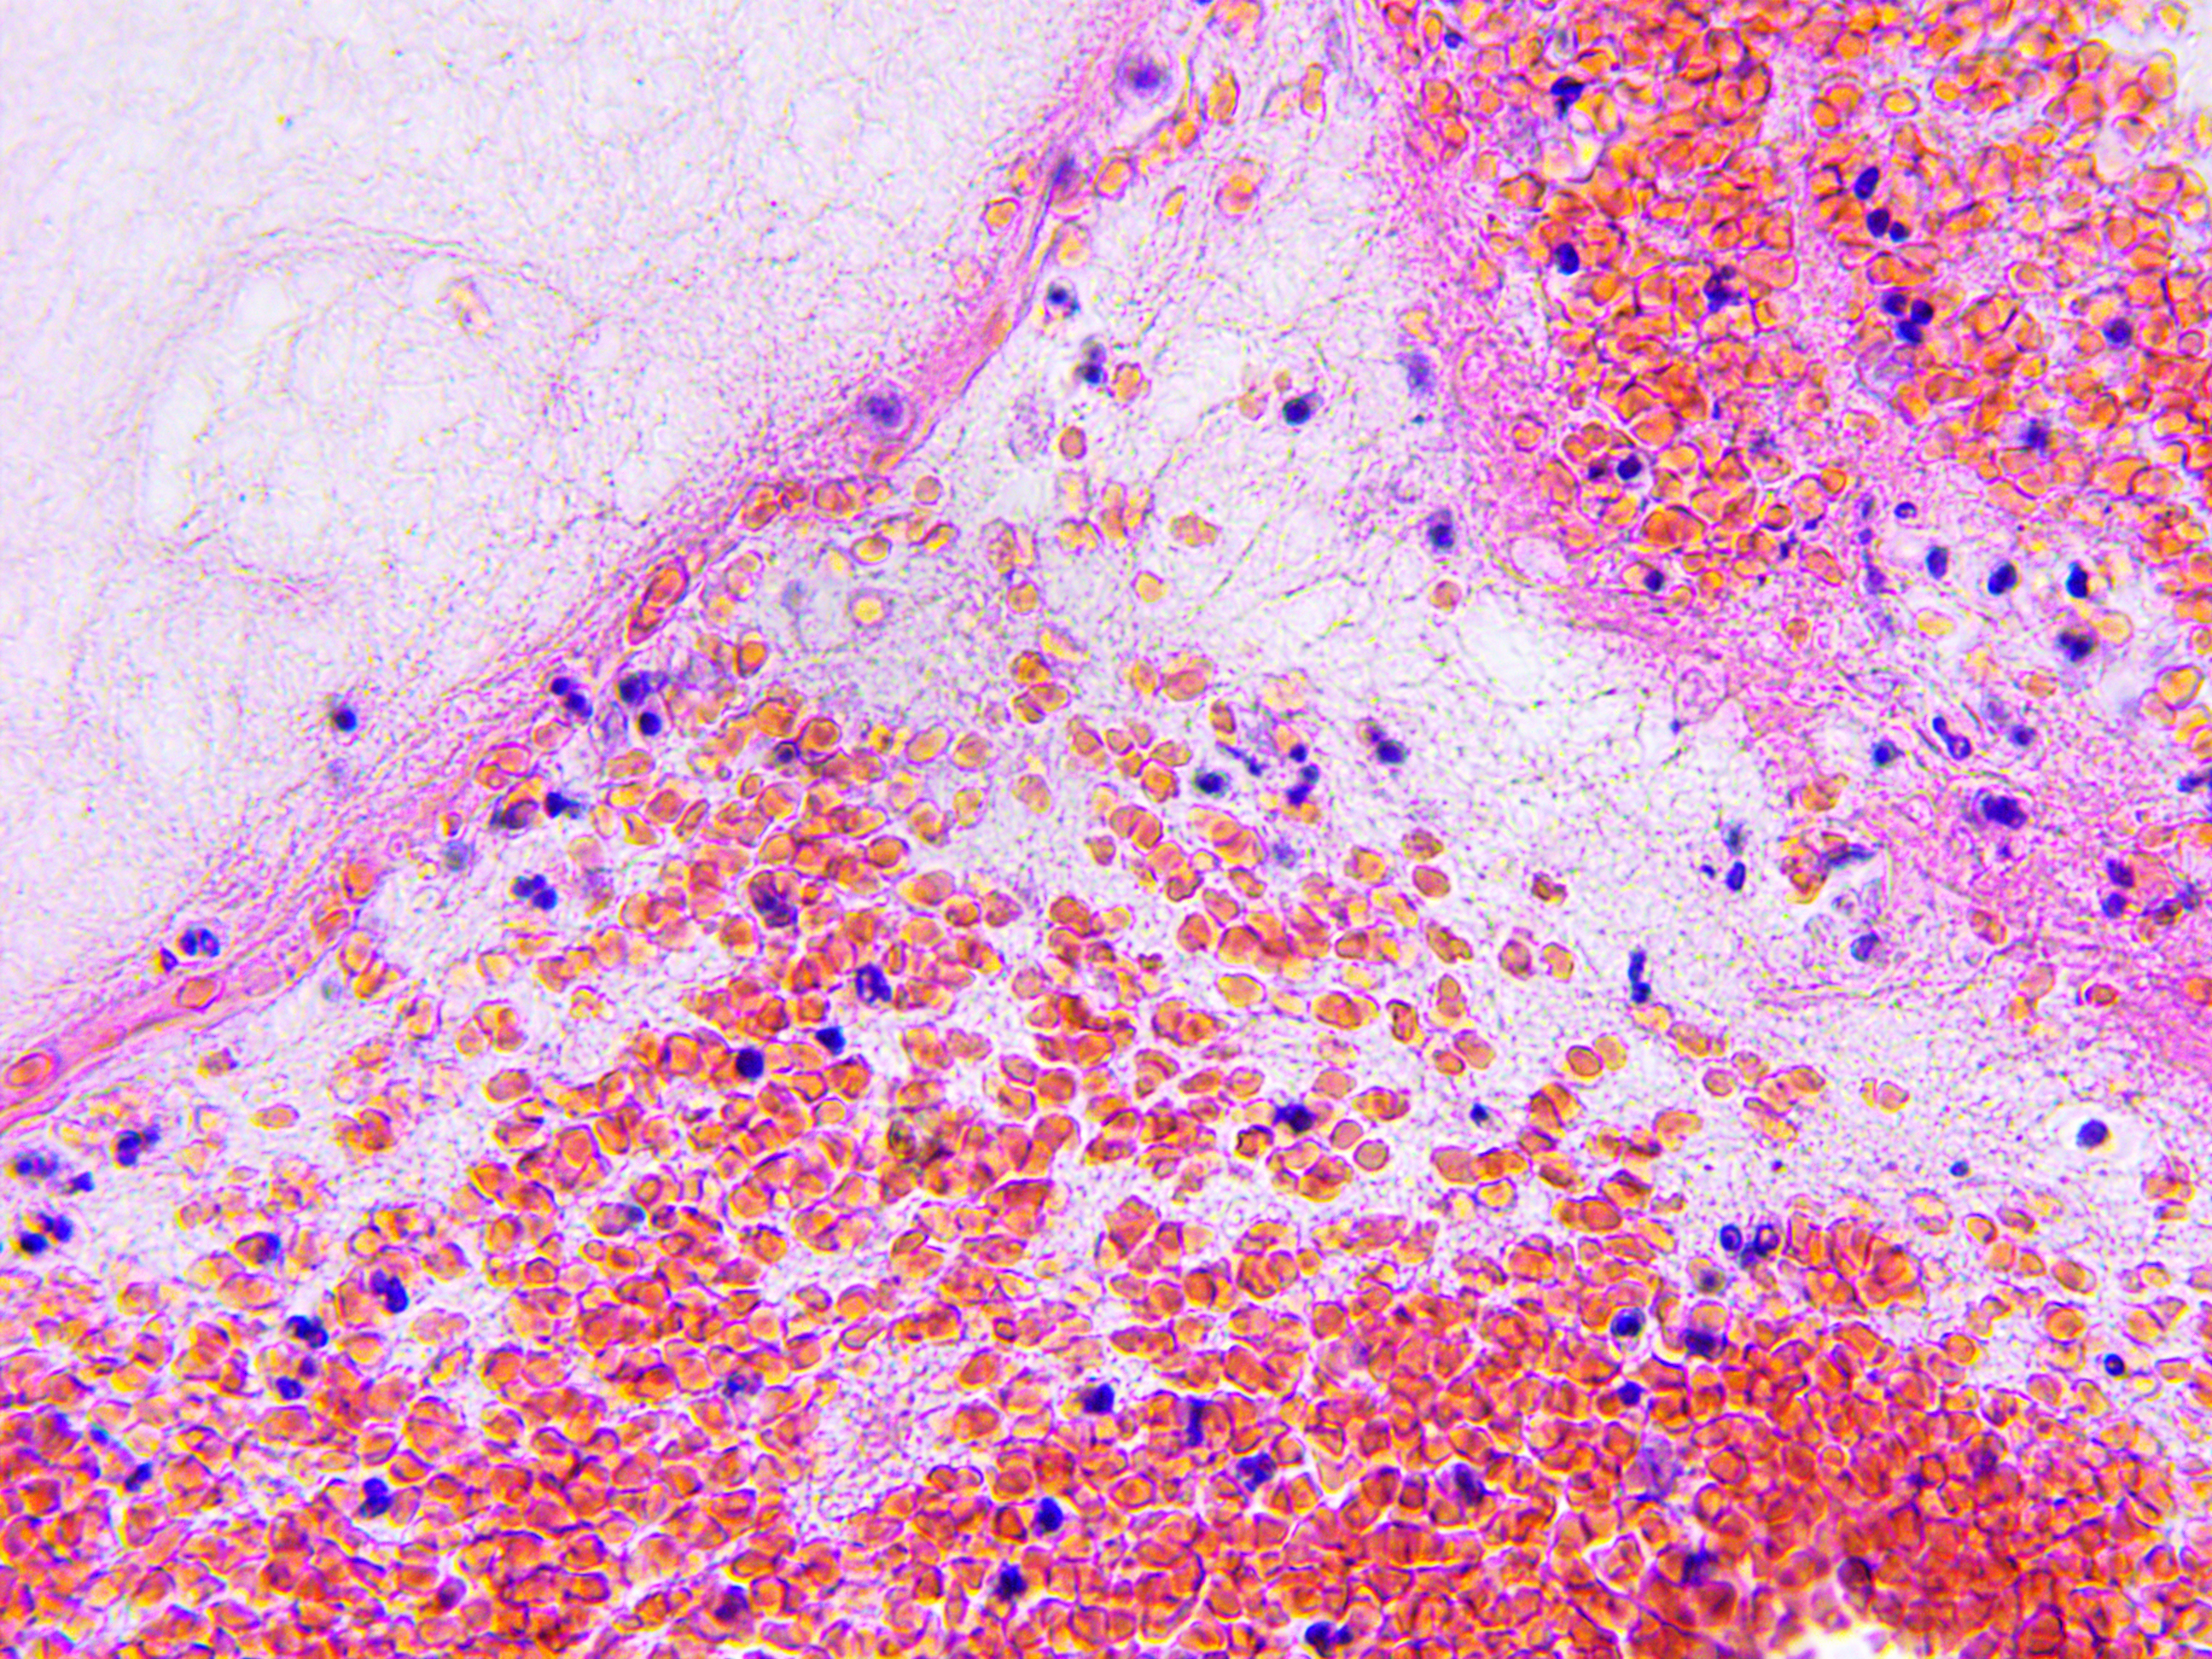

Brain Cancer occurs when abnormal cells in the brain grow in an uncontrolled way. Brain cancers include primary brain tumours, which start in the brain, and secondary tumours (or metastases) which are caused by cancers that began in another part of the body.

The most common malignant (rapidly growing) tumours include: